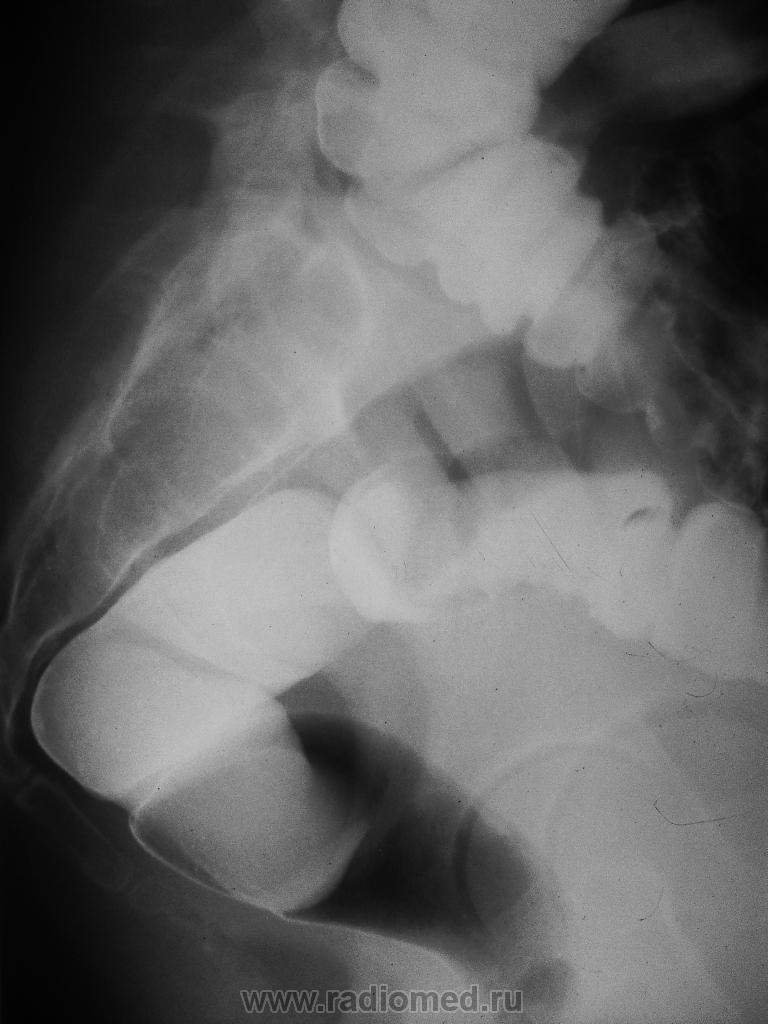

Синдром Линча? Ирригоскопия.

Боли слева в малом тазу, ноющего характера в течение последнего месяца, не температурила. На УЗИ малого таза инфильтрат?опухоль? левого яичника, но кадры УЗИ и все выписки отвезены в онкодиспансер, туда на МРТ и верификацию отправляется в будущий понедельник. Госпитализирована для обследования. Гинеколог считает, что есть шанс воспалительного процесса. Мать девушки умерла от рака яичников.

По снимкам рак сомителен, сигма в полне доступна для колоноскопии.

О воспалительном процессе следует думать в последнюю очередь, поскольку при воспалении как правило идет оттеснение стенки кишки без инфильтрации рельефа слизистой.

Согласен с Виталем- зубчатость нижнего контура ректосигмоидного перехода. Показана  колоноскопия, с забором гистологического материала.

А сколько девушке лет? Скорее середина сигмы - вроде петля такая:

Скорее в дистальной 1/3 сигмы. Конрастирование увы... и проекций маловато.

Кроме отмеченного Вами, следует отметить  неплавный, а уступообразный переход от здоровой стенки к участку инфильтрации.

Девушке 22 года.

Колоноскопия: в 40 см от ануса по задней стенке зона сглаженной интактной слизистой на протяжении 5 см. Биопсия взята, результатов еще нет.